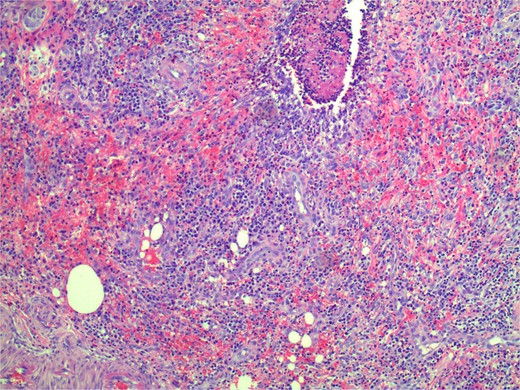

Macroscopic examination of the specimen demonstrated a clot-filled appendiceal lumen and a minimal increase in darkness in the submucosa. Microscopic examination demonstrated focal mucosal ulceration of 2 mm depth, with inflammatory infiltration extending to the muscularis propria, interstitial haemorrhage, and fibrosis (Figs 2 and 3). There was no eosinophilia or significant microscopic inflammatory exudate. This was deemed the most likely origin of bleeding with the final histological diagnosis of focal mild acute appendicitis with focal ulceration to submucosa (Fig. 1).

Microscopic zoomed in view of small ulceration measured to be 2 mm.